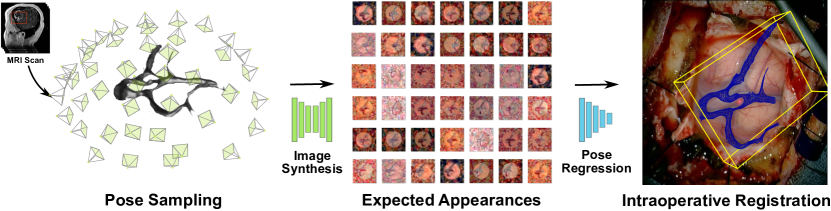

We propose a novel approach for patient-to-image registration that registers the intraoperative 2D view through the surgical microscope to preoperative MRI 3D images by learning Expected Appearances. As shown in Fig. 1, we formulate the problem as a camera pose estimation problem that finds the optimal 3D pose minimizing the dissimilarity between the intraoperative 2D image and its pre-generated Expected Appearance. A set of Expected Appearances are synthesized from the preoperative scan and for a set of poses covering the range of plausible 6 Degrees-of-Freedom (DoF) transformations. This set is used to train a patient-specific pose regressor network to obtain a model that is texture-invariant and is cross-modality to bridge the MRI and RGB camera modalities. Similar to other methods, our approach follows a monocular single-shot registration, eliminating cumbersome and tedious calibration of stereo cameras, the laser range finder, or optical trackers. In contrast to previous methods, our approach does not involve processing intraoperative images which have several advantages: it is less prone to intraoperative image acquisition noise; it does not require pose initialization; and is computationally fast thus supporting real-time use. We present results on both synthetic and clinical data and show that our approach outperformed state-of-the-art methods.

As illustrated in Fig. 1, given a 3D surface mesh of the cortical vessels , derived from a 3D preoperative scan, and a 2D monocular single-shot image of the brain surface , acquired intraoperatively by a surgical camera, we seek to estimate the 6-DoF transformation that aligns the mesh to the image . Assuming a set of 3D points and a set of 2D points in the image , solving for this registration problem can be formalized as finding the 6-DoF camera pose that minimizes the reprojection error: , where and represent a 3D rotation and 3D translation, respectively, and is the camera intrinsic matrix composed of the focal length and the principal points (center of the image) while is a correspondence map and is built so that if a 2D point corresponds to a 3D point where for each point of the two sets. Note that the set of 3D points is expressed in homogenous coordinates in the minimization of the reprojection error.

In practice, we assume constant camera parameters and first sample a set of binary images by randomly varying the location and orientation of a virtual camera w.r.t. to the 3D mesh before populating the binary images with the textures using (see Fig. 1). We restrict this sampling to the upper hemisphere of the 3D mesh to remain consistent with the plausible camera positions w.r.t. patient’s head during neurosurgery.